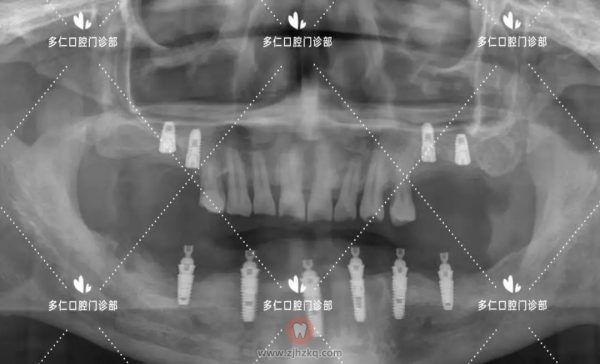

医生建议:27、31、33、34、41、47拔除,15、16、25、26、32、34、36、42、44、46植入植体共10颗,即刻修复,当天戴牙。后期恢复下颌6-6全瓷牙冠12颗,上颌恢复15,16,25,26全瓷牙冠。

术后全景片